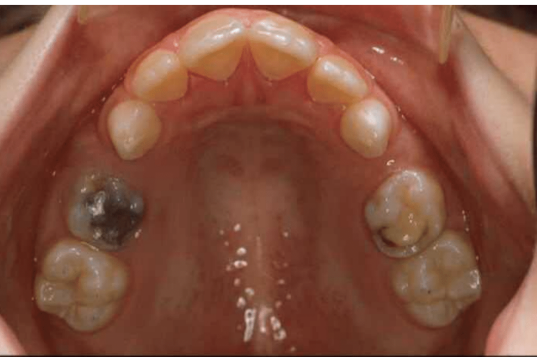

which primary teeth are still present

55, 53

63, 65

which primary teeth have been extracted early

54

64

name for forward movement of teeth into an extractions space

mesial drift

caries risk category

why (3)

high risk

early loss/extraction of primary molars

existing restorations

new carious lesions